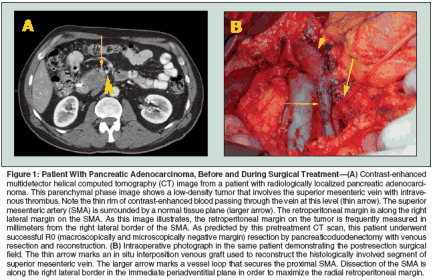

Subtotal pancreatic resection can consist of a left (distal) pancreatectomy or right pancreatectomy, which is usually anatomically described as a pancreaticoduodenectomy or Whipple procedure. For most malignant tumors arising in the pancreatic head and uncinate process, pancreaticoduodenectomy is required to achieve microscopically negative pancreatic parenchymal and retroperitoneal surgical margins. Standard pancreaticoduodenectomy involves resection of the distal stomach, distal bile duct (with cholecystectomy), duodenum, pancreatic head and uncinate process, proximal jejunum, and regional lymph nodes.[22] Gastrointestinal reconstruction following pancreaticoduodenectomy requires enteric, biliary, and pancreatic anastomoses, usually by gastrojejunostomy (or duodenojejunostomy in the case of pylorus-preserving pancreaticoduodenectomy), choledochojejunostomy, and pancreaticojejunostomy (or pancreaticogastrostomy). Technical modifications that have no clearly demonstrated advantage or adverse oncologic impact include pylorus preservation[23] and extended lymphadenectomy.[24,25] Randomized trials of pancreaticoduodenectomy with extended vs standard lymphadenectomy have demonstrated increased morbidity with the extended dissection but no improvement in survival rates.[24,25] As a consequence, most Western surgeons perform either a standard or pyloruspreserving pancreaticoduodenectomy with a standard lymphadenectomy (including peripancreatic lymph nodes) but not extended regional lymphadenectomy. The most oncologically significant and technically demanding step in pancreaticoduodenectomy is the retroperitoneal vascular dissection along the proximal SMA. This step occurs during the final phase of the tumor resection, after division of the stomach, jejunum, bile duct, and pancreas. This step can be technically difficult and associated with a risk of hemorrhage from the pancreaticoduodenal arteries arising from the right posterolateral side of the SMA. In an effort to minimize this risk and save time, many surgeons do not fully mobilize the SMV to adequately expose the SMA and instead choose an easier dissection plane several millimeters to the right of the SMA. Unfortunately, this compromises the radial retroperitoneal margin, which is of critical oncologic significance. Pancreaticoduodenectomy with segmental resection of the SMV or PV is necessary when the tumor is inseparable from the lateral wall of the SMV or PV.[26] When intraoperative findings suggest venous involvement, approximately 80% of patients undergoing pancreatectomy with venous resection have histologic evidence of tumor extension into the vein wall.[26] However, venous resection should be performed only in carefully selected patients who have tumor adherence to the SMV or PV but have no evidence of tumor extension to the SMA or celiac axis (Figure 1). Following pancreaticoduodenectomy with venous resection, patients with pathologic invasion of the SMV or PV do not have an increased frequency of surgical margin or lymph node positivity compared to patients without involvement of the SMV or PV, and patient survival after pancreaticoduodenectomy with venous resection is comparable to that observed in patients with similar tumors that do not require venous resection.[27] Hospital Pancreatectomy Volume and Mortality Rates

For tumors arising in the pancreatic head and uncinate process, the retroperitoneal margin is defined anatomically as the margin between the medial edge of the tumor and the right lateral border of the SMA (Figure 1). During pancreaticoduodenectomy, dissection must occur in the immediate periadventitial plane of the SMA to maximize the radial retroperitoneal margin. As a consequence, the SMA dissection is the most oncologically significant step in pancreaticoduodenectomy. Difficulties in maximizing and pathologically evaluating the retroperitoneal margin include the technical challenge of safe dissection along the proximal SMA and the fact that identification and orientation of the specimen for accurate margin assessment is usually possible only at the time of surgery by combined efforts of the surgeon and surgical pathologist. This margin should be inked in the surgical suite, and the pathology report should describe the distance in millimeters between the tumor and the inked retroperitoneal margin; retrospective evaluation of this margin is not possible. Details of the procedure for margin assessment are outlined in the sixth edition of the AJCC Cancer Staging Manual.[42] Pancreatectomy margins (especially the retroperitoneal margin) should be classified by the surgeon after integration of the operative findings and the microscopic surgical margin findings in the final pathology report. All pancreatic resections should be class- ified according to residual disease status (termed "R" factor): R0, no gross or microscopic residual disease; R1, microscopic residual disease (microscopically positive surgical margins with no gross residual disease); and R2, grossly evident residual disease. The pathologist cannot usually differentiate an R1 (microscopically positive) from an R2 (grossly positive) retroperitoneal margin in the absence of information regarding the retroperitoneal dissection, which should be included in the operative note. The R designation should appear in the final pathology report and should be consistent with the dictated operative note. For example, if the surgeon states that gross tumor was encountered when completing the retroperitoneal dissection, a positive histologic margin should result in the R2 designation in the final pathology report. In the absence of this information being included in the operative report, the proper R designation cannot be determined. The difficulty in differentiating R1 from R2 resections has significant implications for clinical trials examining the potential survival advantage of adjuvant or neoadjuvant therapies.